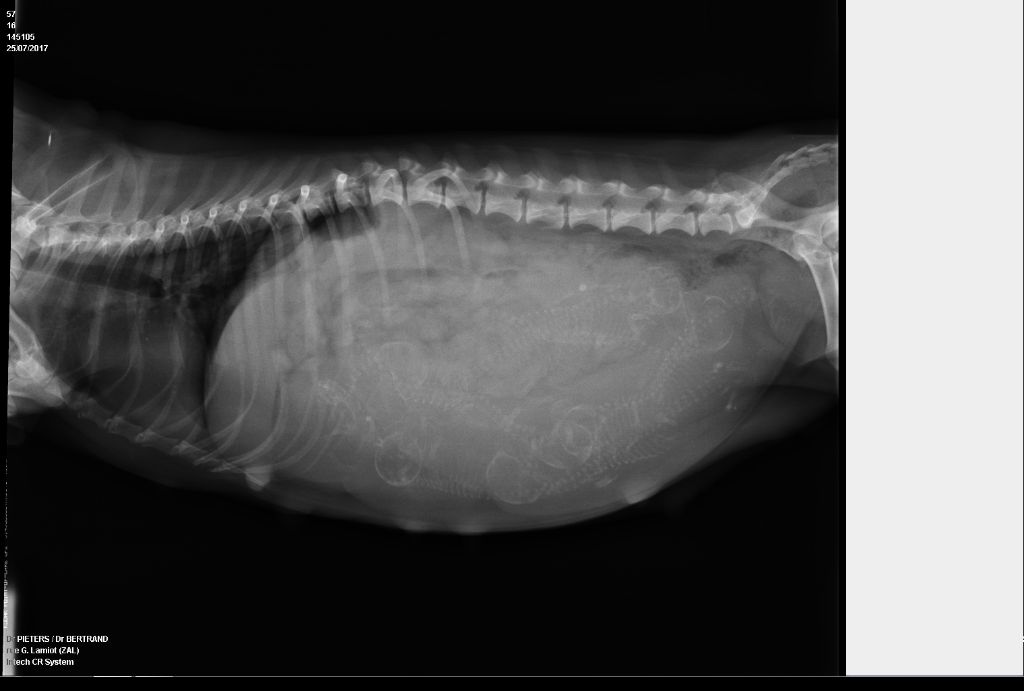

radiographie de Judith et Ovide

02/08/2017